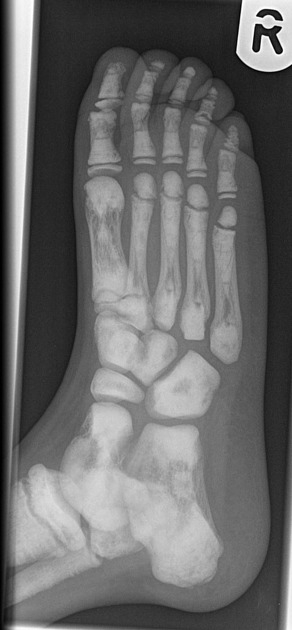

Obrazowanie stanowi podstawowy element diagnostyki osteopetrozy. Badanie RTG jest wystarczające do wstępnego rozpoznania, umożliwiając identyfikację typowych zmian, takich jak:

- uogólniona osteoskleroza (marble bone);

- obraz „kości w kości” (bone-in-bone);

- „kanapkowe” trzony kręgów (sandwich vertebrae);

- deformacja kolby Erlenmeyera w przynasadach kości długich.

Tomografia komputerowa umożliwia ocenę stopnia sklerotyzacji, deformacji czaszki i kanałów nerwowych oraz wykrywanie złamań patologicznych. Rezonans magnetyczny pozwala ocenić stopień zajęcia szpiku i ewentualne neuropatie nerwów czaszkowych, w tym ucisk nerwów wzrokowych i słuchowych.